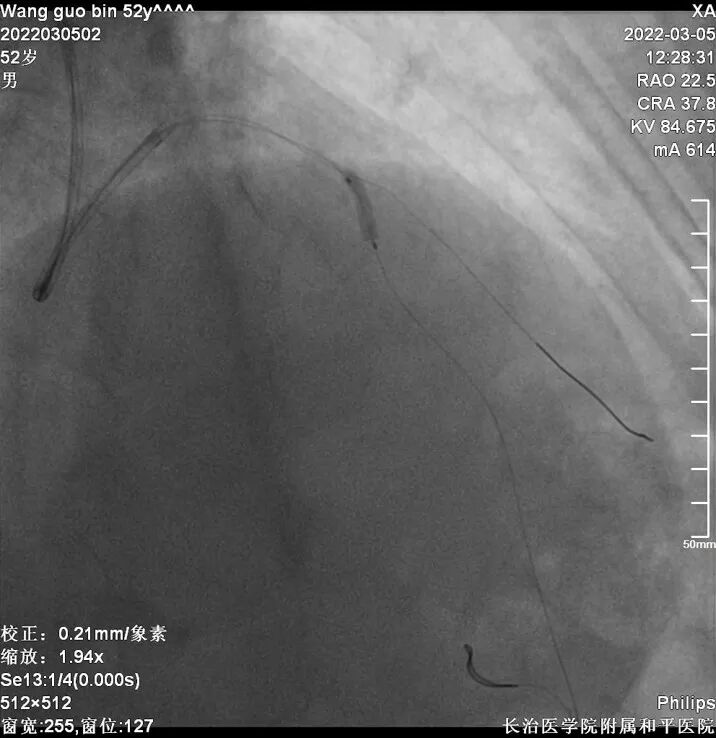

冠脉造影

CAG

干预右冠

介入经过及结果

6FEBU3.5Guiding、Runthrough导丝、Sion导丝、2.0x15mm球囊